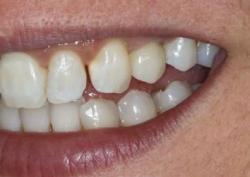

Примеры работ синус-лифтинга

Ежедневно мы восстанавливаем улыбку и уверенность в себе 5–7 пациентам.